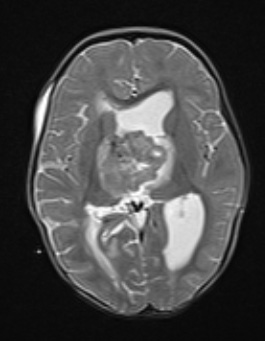

20A4 ATRT (NP24-888) T2W axial - Copy

The tumor appears to have a thalamic component.